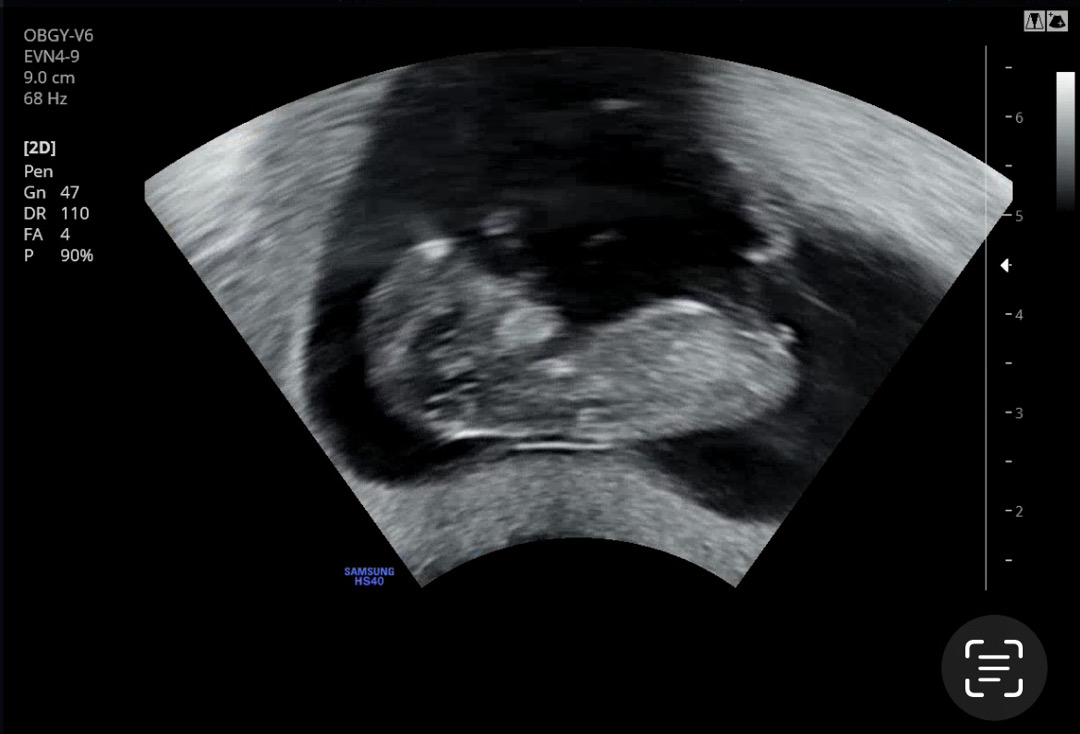

각도법 봐주실분 🙏 투표한번만 해주세욥🙏

최대한 잘나온 사진으로 첨부해보아요!! 간단히 투표해주심 감사드리겠습니다 🥹 댓글에도 사진 하나 더 올릴게요!